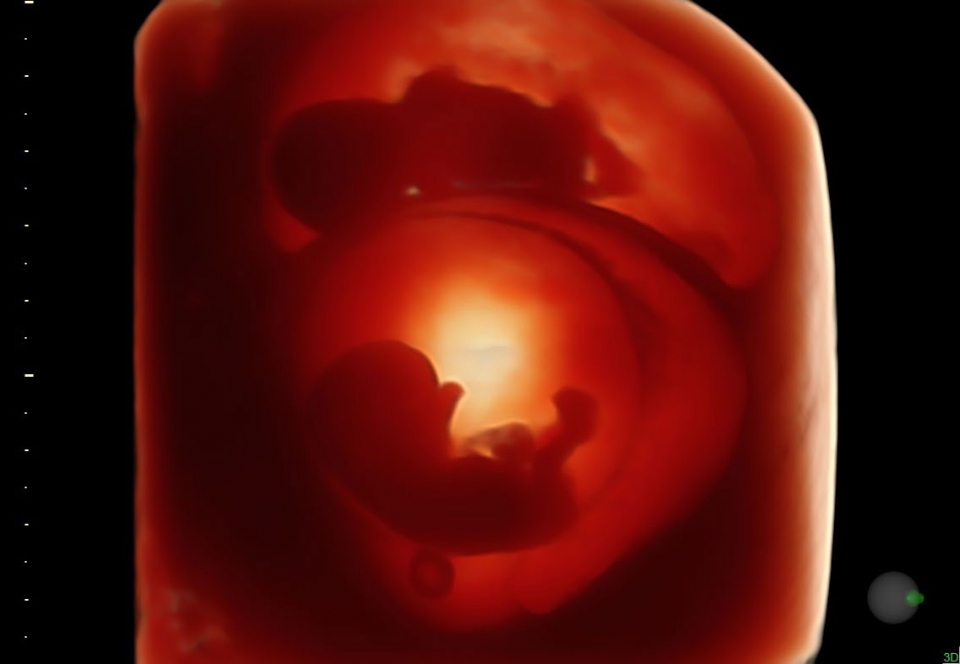

УЗИ аппарат Voluson S10 позволяет проводить обследования высочайшего уровня с максимальной точностью диагностики. Благодаря технологии Voluson Core Architecture достигнут высокий уровень качества изображений с возможностью последующей обработки и анализа даже после проведения скрининга. Технология HDlive делает изображения удивительно реалистичными и объемными.

• HDlive в 3D и 4D - режим перемещаемого виртуального источника освещения - "виртуальная фетоскопия"